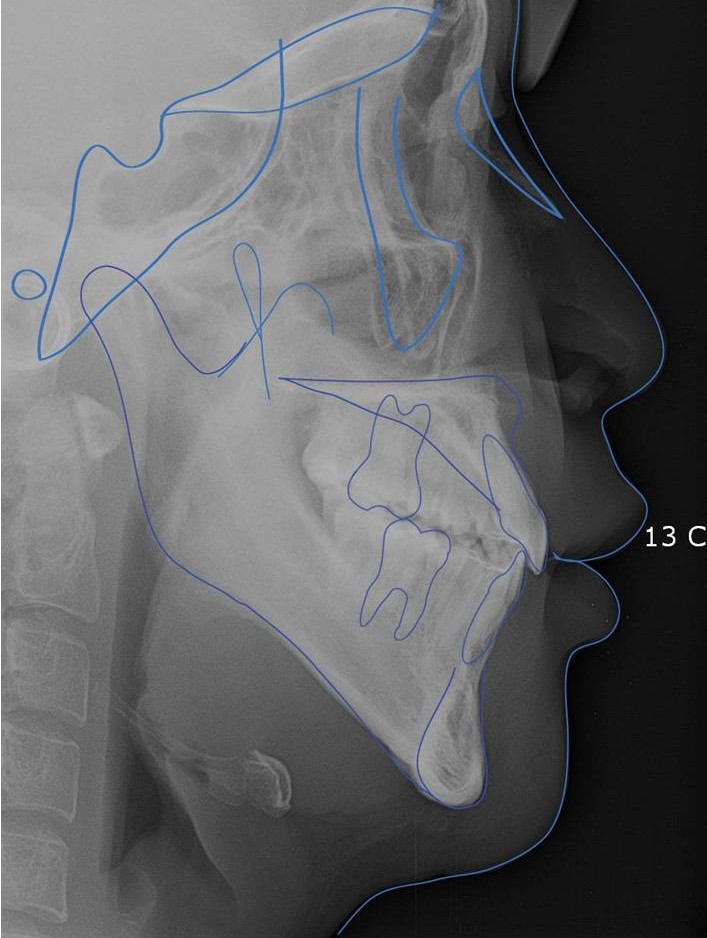

1. 3D CT를 통해 골격과 치아의 위치를 입체적으로 파악합니다.

교정치료를 진행하기 전에 3D CT를 통해 안면 골격과 치열의 입체적인 분석을 시행합니다.

입체적 골격 계측

CT 분석을 기반으로 골격의 위치변화를 정밀하게 계측합니다.